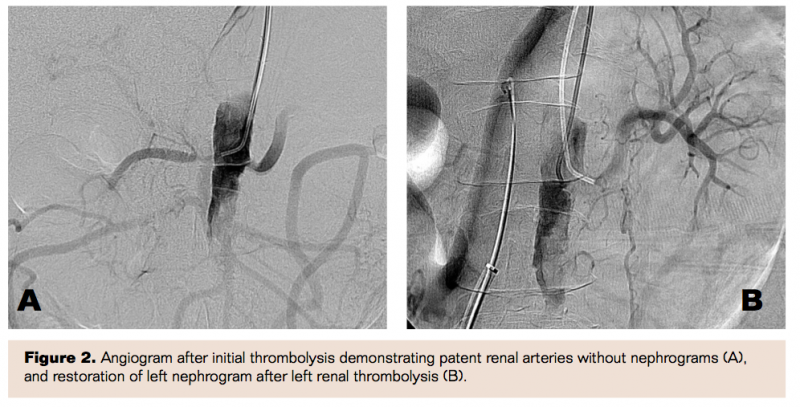

Six hours after initiation of lysis, the patient became acutely oliguric and hypertensive. Given her hypertension and low fibrinogen level (50 mg/dL), thrombolysis was stopped. There was concern about the potential for retrograde propagation of the aortic thrombus with concomitant thrombosis of the renal arteries. The patient was taken urgently to the operating room where an aortogram demonstrated no increase in aortic thrombus and patent renal arteries; however, there were no nephrograms, indicating lack of renal parenchymal perfusion (Figure 2A). This was presumably secondary to microemboli from ongoing lysis. At this point the right femoral vein was cannulated and a 10 mm x 4 cm balloon was used to occlude the right renal vein. The ipsilateral renal artery was then similarly occluded with a 5 mm x 4 cm balloon and a total of 10 mg of tPA was infused distally into the kidney over 20 minutes. Thereafter the venous balloon was deflated and the kidney flushed with heparinized saline and nitroglycerin 200 mcg. The arterial balloon was let down. An identical procedure was then performed for the contralateral kidney. Completion angiogram demonstrated significantly improved renal parenchymal blood flow (Figure 2B). A wire was then passed through the aortic occlusion into the right external iliac artery. Balloon angioplasty of the aorta and right common iliac artery was used to dilate the flow channel. A 20 cm infusion catheter was placed through the flow channel with 5 cm above the renal arteries. Thrombolysis was initiated again with tPA 0.5 mg/hr.